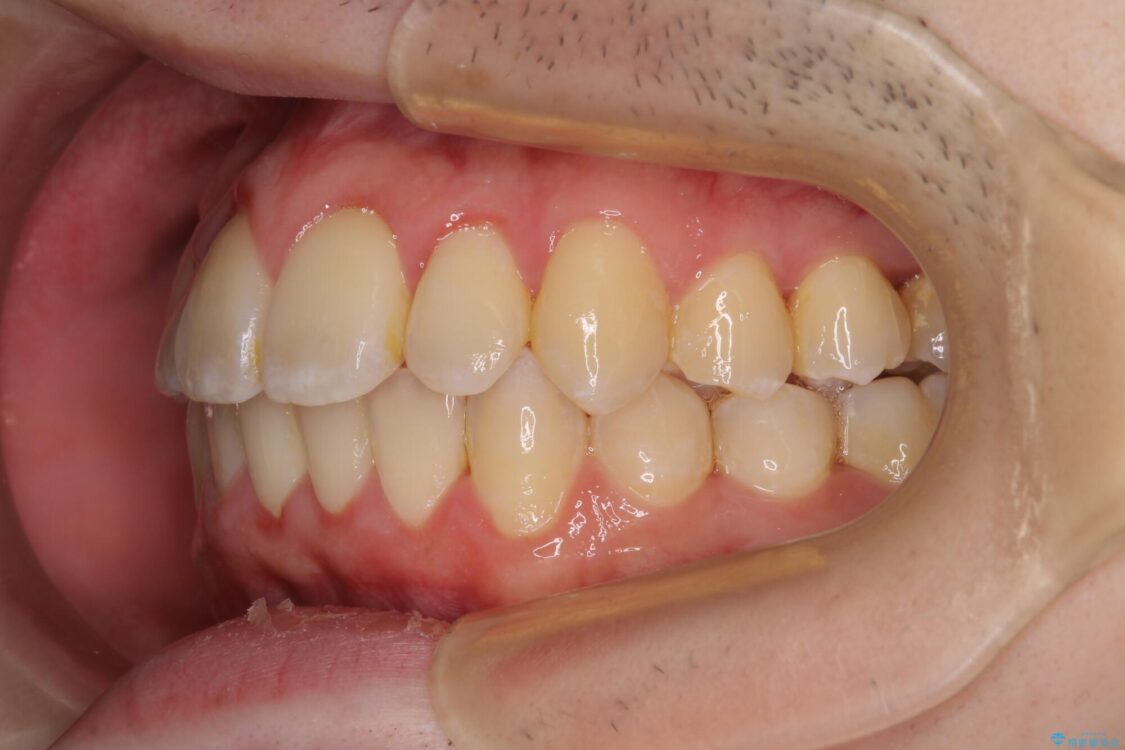

治療後

• 全顎的なクロスバイト 補助装置を用いてワイヤー矯正 治療後画像

治療後について

シザーズバイトは強く咬合する奥歯を移動させるため、多くの場合においてワイヤー矯正の装置のみでは改善が困難となります。

奥歯の咬み合わせ改善は治療初期からしっかりとアプローチする必要があるため、補助装置を積極的に利用します。